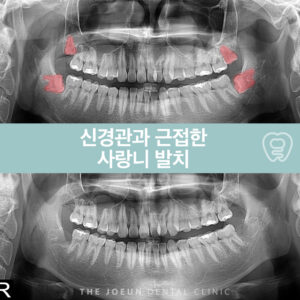

계명대치과 하치조 신경과 가까운 사랑니 발치

계명대치과 하치조 신경과 가까운 사랑니 발치   청소년기와 성인 사이 즈음, 뒤늦게 모습을 드러내기 시작하는 사랑니라고 부르는 제3대구치는 대개 10대 후반에서 20대 초반 사이에 자라기 시작하는데 과거에는 질긴 음식을 씹는데 도움을 주는 역할을 했지만 식생활이 부드러워지면서 그 기능은 점차 줄어들었는데요. 이로 인해 사랑니는 개인에 따라 아예 나지 않거나 1개에서 많게는 더보기…